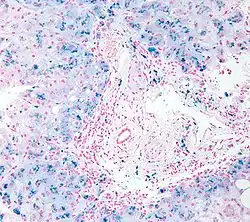

Cerebrospinal fluid specimen stained with Perls Prussian blue showing iron containing macrophage (stained blue) surrounded by erythrocytes (stained red)

In histology, histopathology, and clinical pathology, Perls Prussian blue is a commonly used method to detect the presence of iron in tissue or cell samples.[1]: 235 [2][3][4] Perls Prussian Blue derives its name from the German pathologist Max Perls (1843–1881), who described the technique in 1867.[2] The method does not involve the application of a dye but rather causes the pigment Prussian blue to form directly within the tissue.[5] The method stains mostly iron in the ferric state which includes ferritin and hemosiderin, rather than iron in the ferrous state.[6]